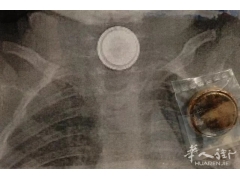

罗马4岁儿童突发腹痛,竟因误食了纽扣电池!

近日,罗马一名4岁儿童在家玩耍时,...

罗马一名4岁男孩误吞电池被医生检查发现

〓意大利华人街(微信订阅号:huarenjie...